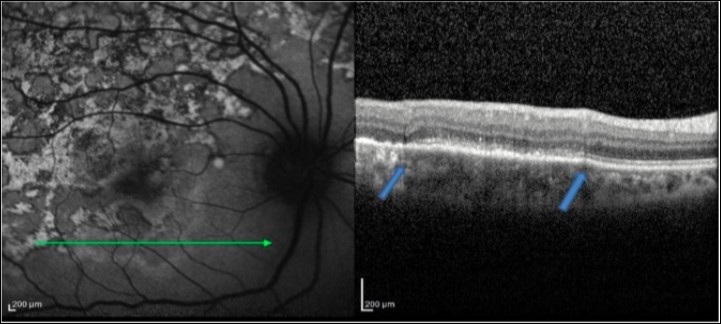

Figure 2.FAF (left) and corresponding eye-tracked SD-OCT image (right) of patient 1 an acute stage of the right eye shows fuzzy area of hyperreflectivity in the outer retinal layers involving the RPE, photoreceptor outer segment tips (POST), photoreceptor inner segment–outer segment (IS/OS) junction, external limiting membrane (ELM), and the outer nuclear layer (ONL) with vitreal and choroidal cells

Figure 3.FAF (left) and corresponding eye-tracked SD-OCT image (right) of patient 1 during healing stage of the right eye shows hyperreflective knobbly elevations of the outer retinal layers. The RPE, the POST, IS/OS junction, and the ELM could not be distinguished. The ONL appeared normal with increased reflectance from the choroidal layers.

Figure 4.FAF (left) and corresponding eye-tracked SD-OCT image (right) of patient 1 healed stage of the left eye shows showed loss of RPE, POST, IS/OS junction, and ELM with increased reflectance from the choroidal layers. absent of the choroidal and intraretinal cells.

1. In an acute lesion of MCS, there was an ill-defined area of increased autofluorescence around the lesion. The SD-OCT passing through the area showed a localized, fuzzy area of hyperreflectivity in the outer retinal layers involving the RPE, photoreceptor outer segment tips (POST), photoreceptor inner segment–outer segment (IS/OS) junction, external limiting membrane (ELM), and the outer nuclear layer (ONL). The lesion was localized external to the outer plexiform layer with a mild distortion of the inner retinal layers. Choroidal and intra retinal layer cells infiltrate with corresponding increase thickness of choroid and inner retinal layers more obvious in EDI-OCT. There was no increased backscattering from the inner choroid.

2. As the lesions started to heal, they became well defined and acquired a thin border of hypoautofluorescence while remaining predominant hyperautofluorescent centrally. The SD-OCT scan through the hyperautofluorescent area showed disappearance of the hyperreflective fuzzy areas that were replaced by irregular, hyperreflective knobbly elevations of the outer retinal layers. The RPE, the POST, IS/OS junction, and the ELM could not be distinguished. The ONL appeared normal. At this stage, there was an increased reflectance from the choroidal layers due to attenuating RPE–photoreceptor complex.

3. As the lesions healed further over the next 3–6 months, they appeared stippled with predominantly hypoautofluorescence. The SD-OCT scan showed loss of RPE, POST, IS/OS junction, and ELM with absent of the choroidal and intraretinal cells. The increased reflectance from the choroid persisted.